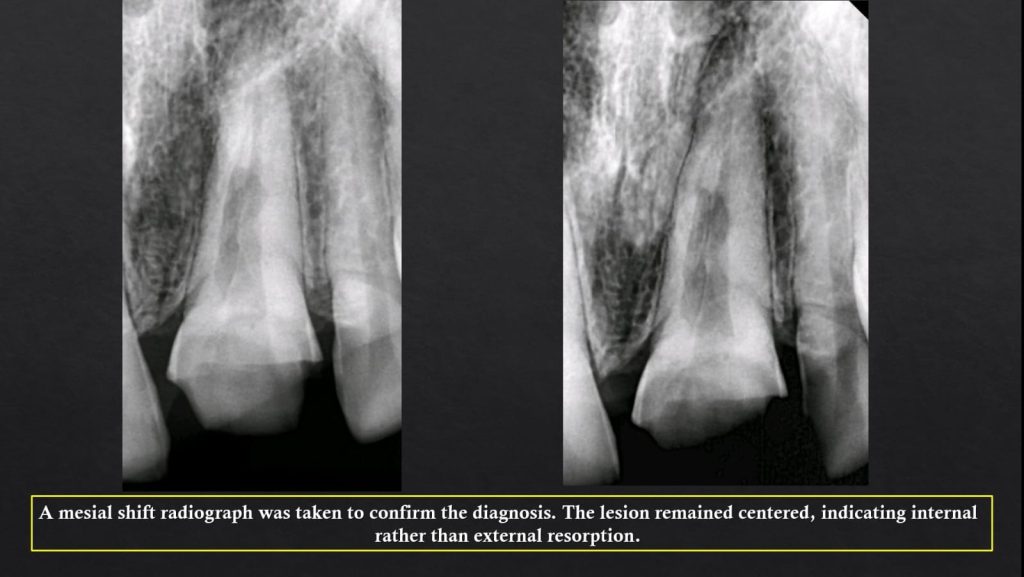

Clinically , IRR may go unnoticed until detected radiographically. However traditional radiographs can miss early lesions, whereas CBCT offers precise three-dimensional evaluation, especially in complex or perforated cases. Histologically, resorptive areas may show granulation tissue or bone-like deposits depending on the type. Management focuses on eliminating the pulp tissue and sealing the resorptive defect using advanced techniques such as warm gutta-percha, bioceramic sealers , or regenerative protocols when perforation is present.